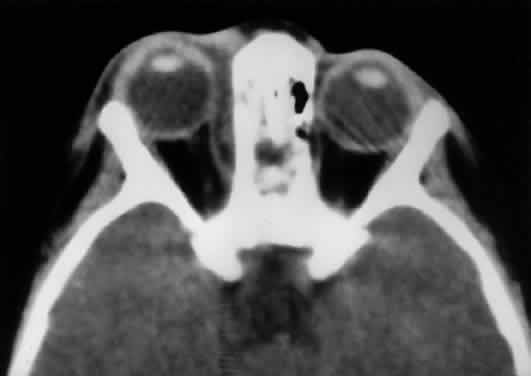

Before giving off the ophthalmic artery, the ICA has several minor branches that supply the meninges, including the dura of the lateral wall of the CS. An abnormal communication between the arterial and venous supply of the CS results in either a carotid-cavernous fistula or a dural-sinus fistula (Fig. 18A). Because of the larger caliber of the ICA, a carotid-cavernous fistula is usually symptomatic secondary to a high flow state, possibly manifesting as orbital/ocular ischemia and increased intraocular pressure. This type of fistula is most commonly encountered in younger patients after blunt trauma and may require invasive neuroradiologic treatment (Fig. 18B). Conversely, a dural-sinus fistula is typically a low-flow state because the abnormal communication forms between the small-caliber dural arterial feeders of the lateral CS wall and the venous plexus of the CS. Such fistulas are usually seen in older individuals as a spontaneous event. Depending on the severity of symptoms, most dural sinus fistulas are simply followed by observation because of the high rate of spontaneous closure.

Fig. 18. Carotid-cavernous fistula. A. Clinical photograph demonstrating tortuosity of the arteriolized episcleral veins, extending up to the limbus (the vascular congestion of conjunctivitis usually ends 1 mm short of the limbus). B. Axial CT shows the difference in caliber between the uninvolved superior ophthalmic vein and the involved vein (arrows). C. Coronal image likewise shows the difference in venous size (arrows). Also note the enlargement of the extraocular muscle on the involved side, indicative of orbital congestion. The superior ophthalmic vein is always found beneath the superior rectus muscle, to which it is tethered by a hammock-like fascial slip. On the involved side, orbital congestion and enlargement of the vein cause distortion of this anatomic relation. D. Parasagittal arteriography image of a different patient shows abnormal arterial filling of the CS, extending anteriorly into the orbit through an engorged superior ophthalmic vein (SOV).